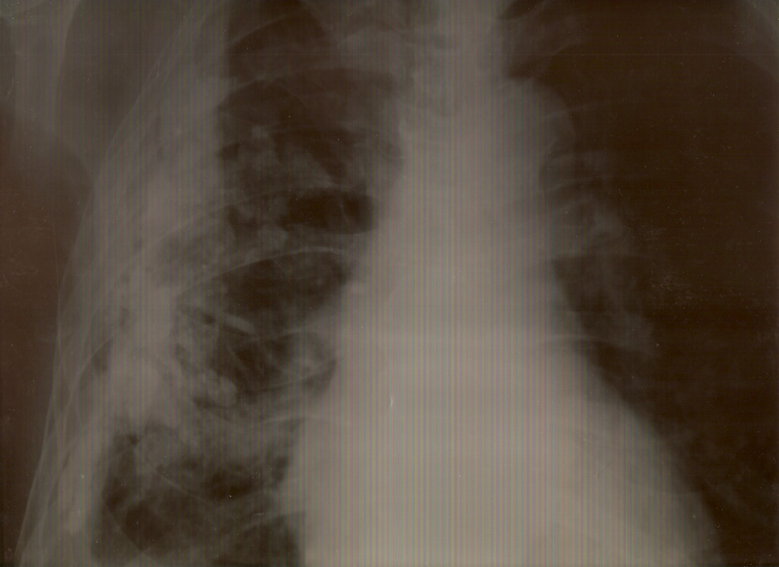

кальцификация перенесенного плеврита

Обсуждалось здесь viewtopic.php?f=24&t=995